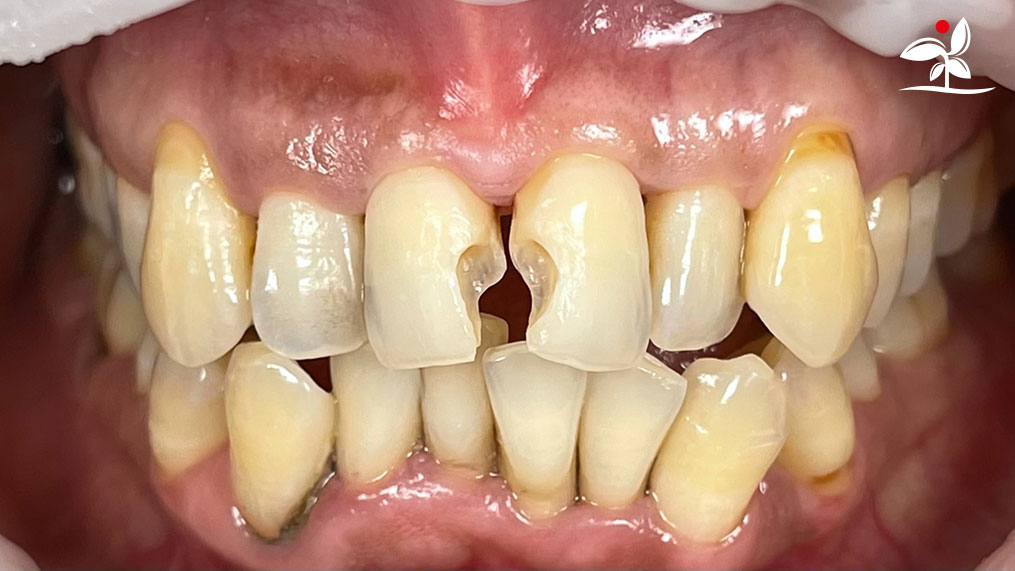

Restoration of Class IV Lesions using Naturomimetic Layering Technique (NLT) and Bioactive Restorative Materials

Dr Aung Pyae Phyo, Myanmar

With the growing awareness about the health, function and aesthetic benefits of preserving natural tooth structure, patients are now globally demanding for aesthetic dentistry with minimally invasive procedures that has a low biological cost. This public demand has encouraged logical clinicians to adopt to the minimally invasive cosmetic dentistry (MiCD) concept and its treatment protocol [1] in their practice. The author has been using MiCD concept and its treatment protocols since 2017, which

include the methods of treatment that are simple, fast, predictable and healthy. In aesthetic restoration, the tooth color restorative materials placement technique is one of the most challenging, confusing and frustrating areas to learn owing to the multiple techniques that have been proposed by many clinicians and replicating such techniques in practice is not always as easy as they are marketed in dentistry. Natural teeth are complex in structure and hard to simulate due distribution of colors through enamel and dentin [2]. Aesthetic restoration strategies should follow proper understanding of defects, right selection of restorative materials along with their proper application, finishing, texturing and polishing [2].